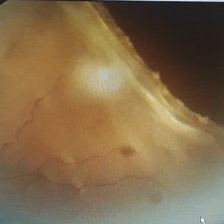

Closed Funnel Retinal Detachment

Fundus phtograph of an 51-year-old man with closed funnel rhegmatogenous retinal detachment presented to our department 6 weeks after cataract surgery. Posterior capsule rent noticed with vitreous in anterior chamber, condensed vitreous tag is incarcerated in side port wound.

Photographer: Dr Aliya Sultana , Assistant Professor,Sarojini Devi Eye Hospital, Hyderabad, Telangana. India.